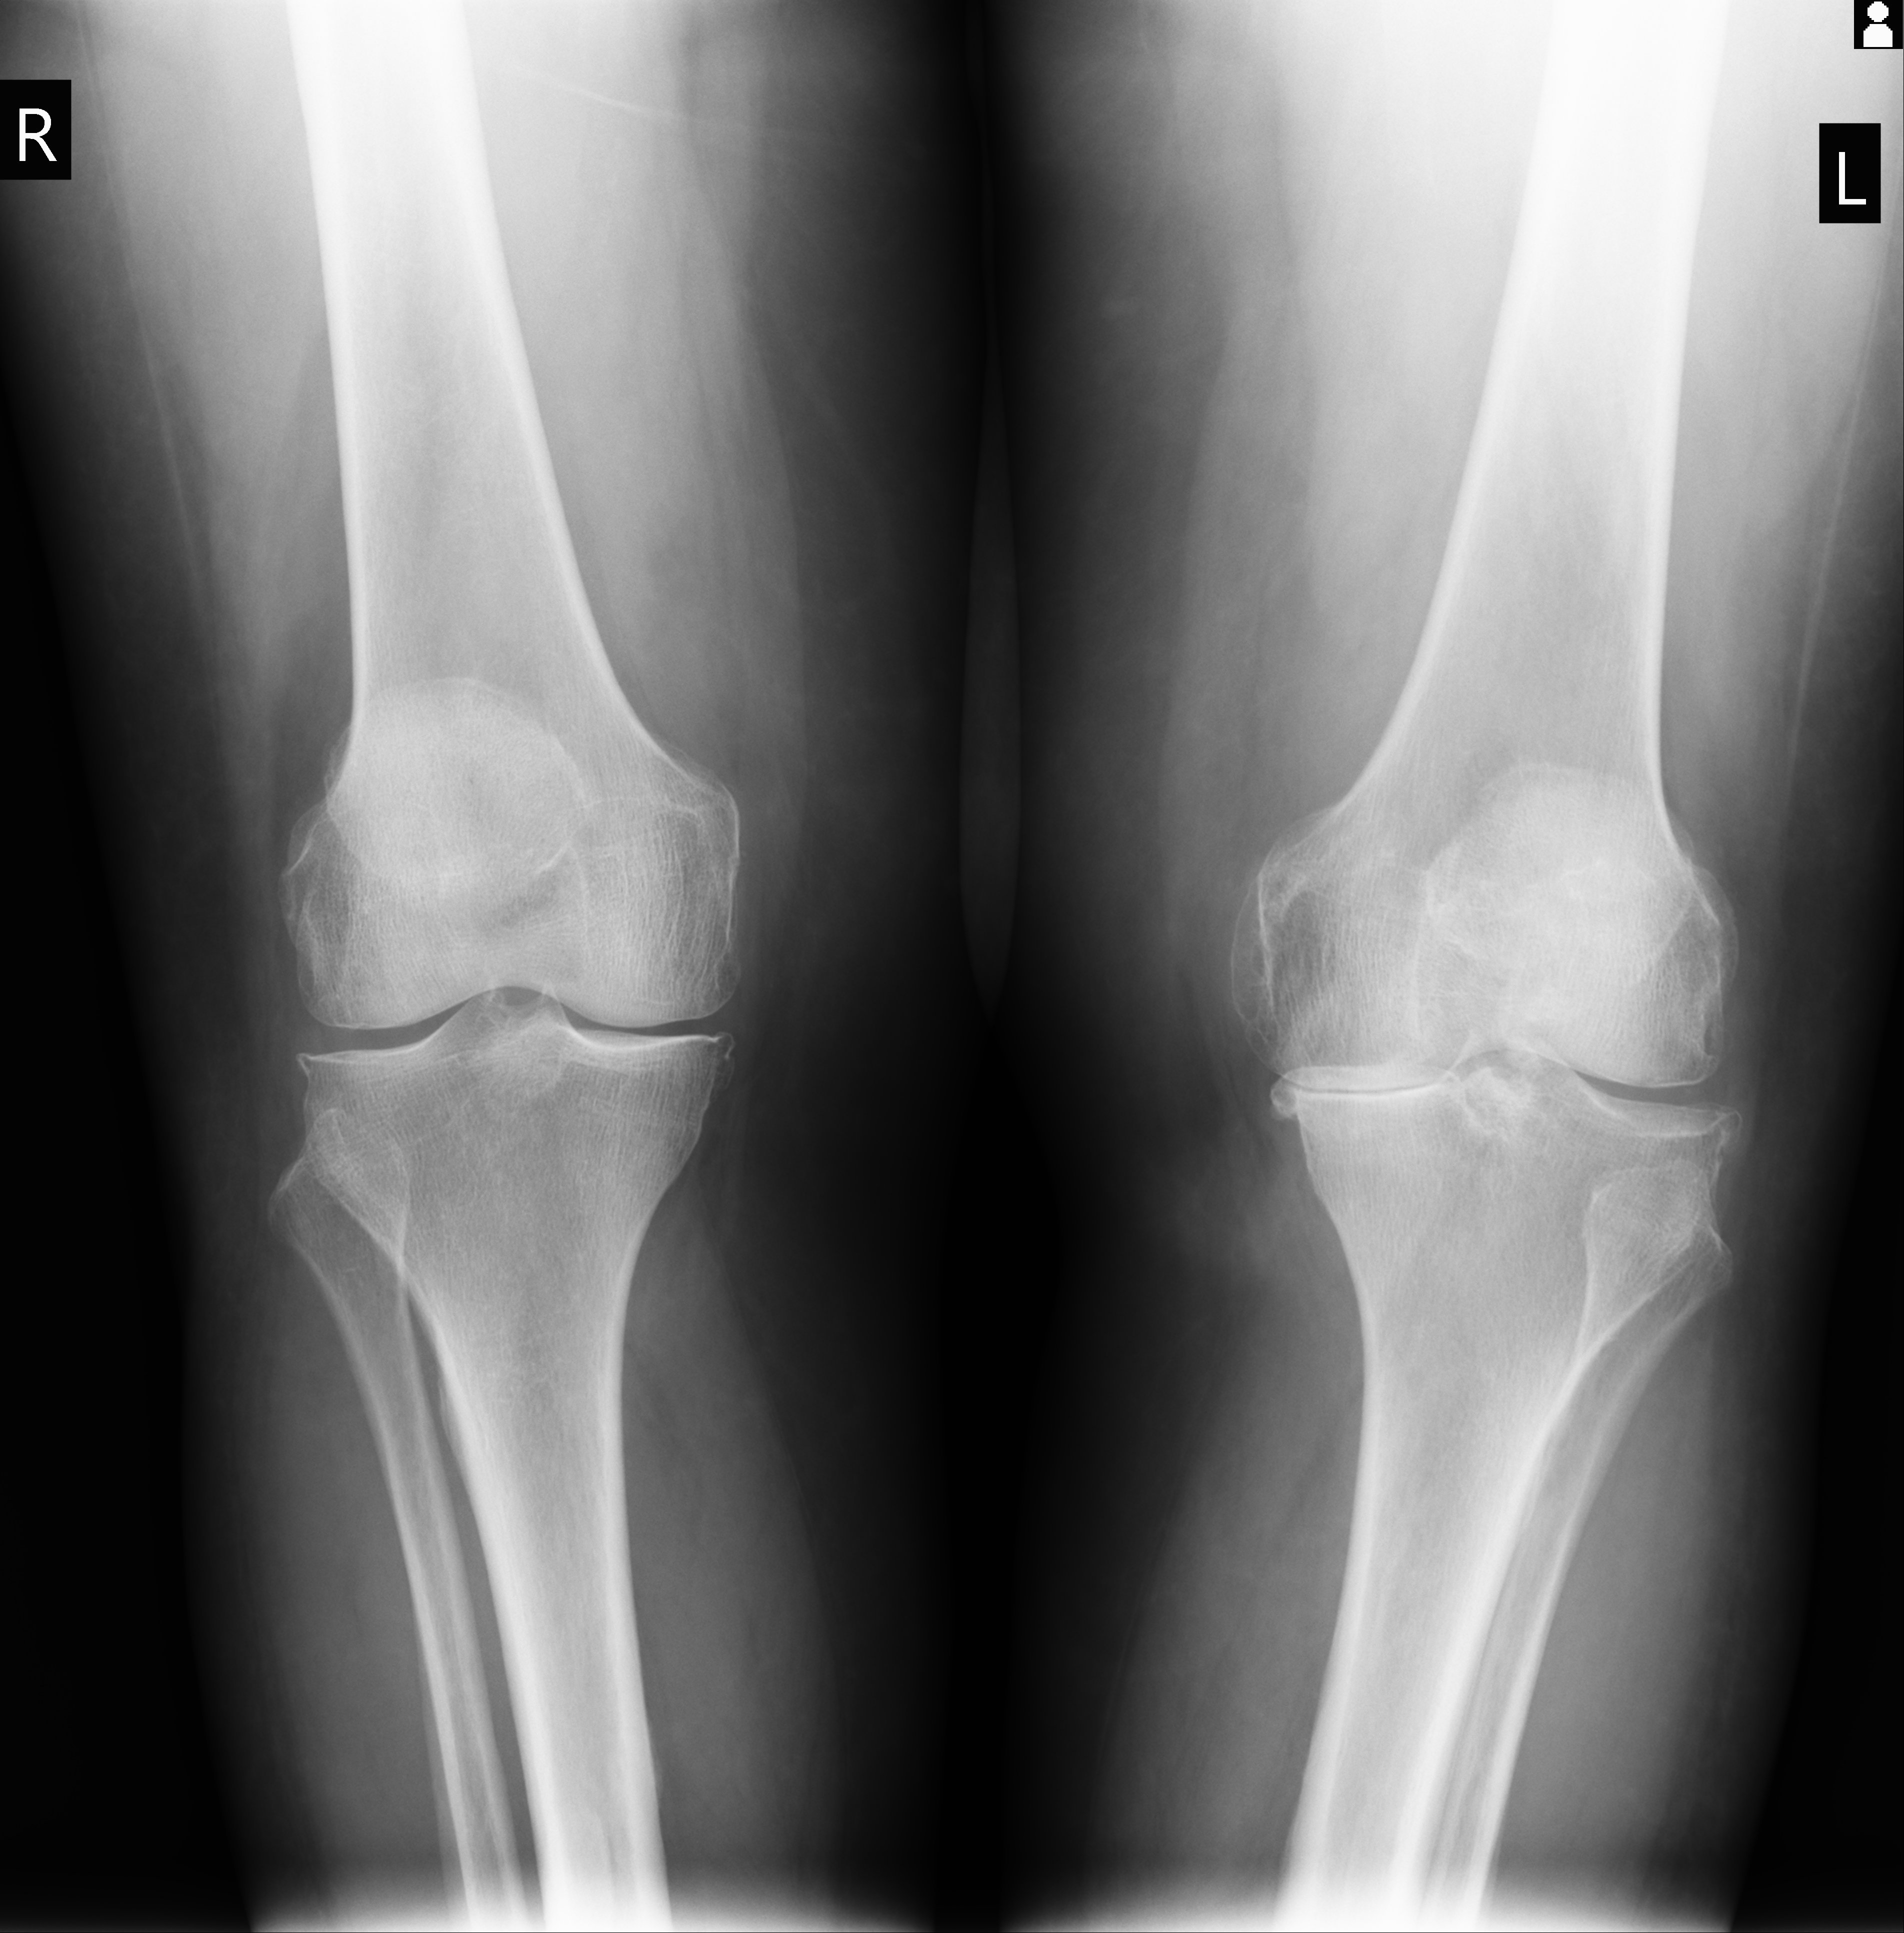

U modernoj ortopediji degenerativne promjene klasificiraju se prema radiološkim kriterijima, a stupanj oštećenja određuje terapijski pristup.

U specijaliziranoj ortopedskoj poliklinici dijagnoza uključuje klinički pregled, ultrazvučnu dijagnostiku, rendgensko snimanje i, ako je potrebno, magnetsku rezonancu.

Danas moderna ortopedija ima precizne dijagnostičke metode koje omogućuju rano otkrivanje degenerativnih promjena.

Najčešće metode su: